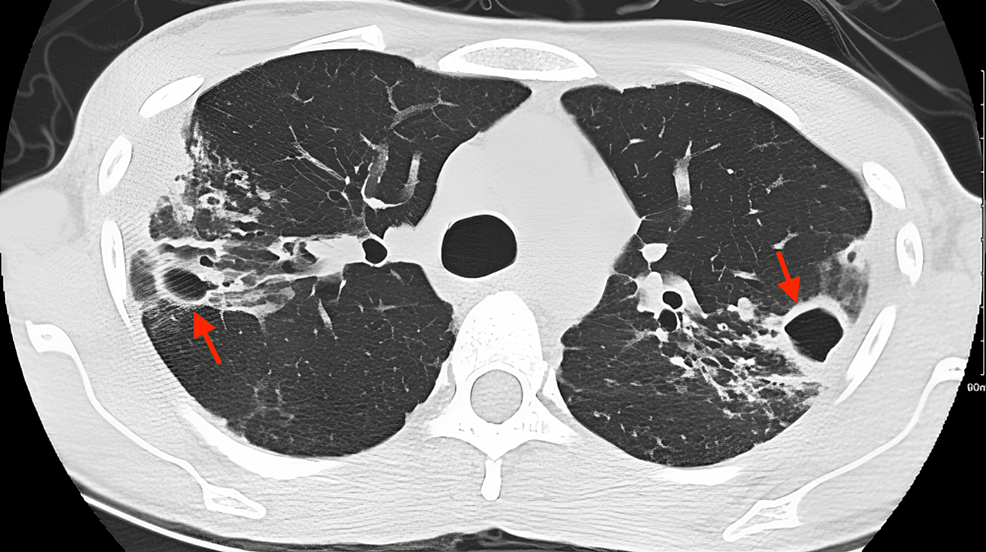

247Lu Mycobacterium Avium Complex (MAC) Lungs

pulmonary mycobacterium avium complex (MAC) infection pacs What Is Mac Lung Disease Mac is a group of common bacteria. When a person gets a lung infection from mac germs, they have mac lung disease. It can cause nodules or cavities in the. Describe the pathophysiology of mycobacterium avium intracellulare. Mac lung disease is a bacterial infection that can damage the lungs and cause symptoms like cough, fatigue and weight loss. Here are. What Is Mac Lung Disease.

247Lu Mycobacterium Avium Complex (MAC) Lungs What Is Mac Lung Disease It can cause nodules or cavities in the. Describe the pathophysiology of mycobacterium avium intracellulare. Mac is a group of common bacteria. When a person gets a lung infection from mac germs, they have mac lung disease. Mac lung disease is a bacterial infection that can damage the lungs and cause symptoms like cough, fatigue and weight loss. Here are. What Is Mac Lung Disease.